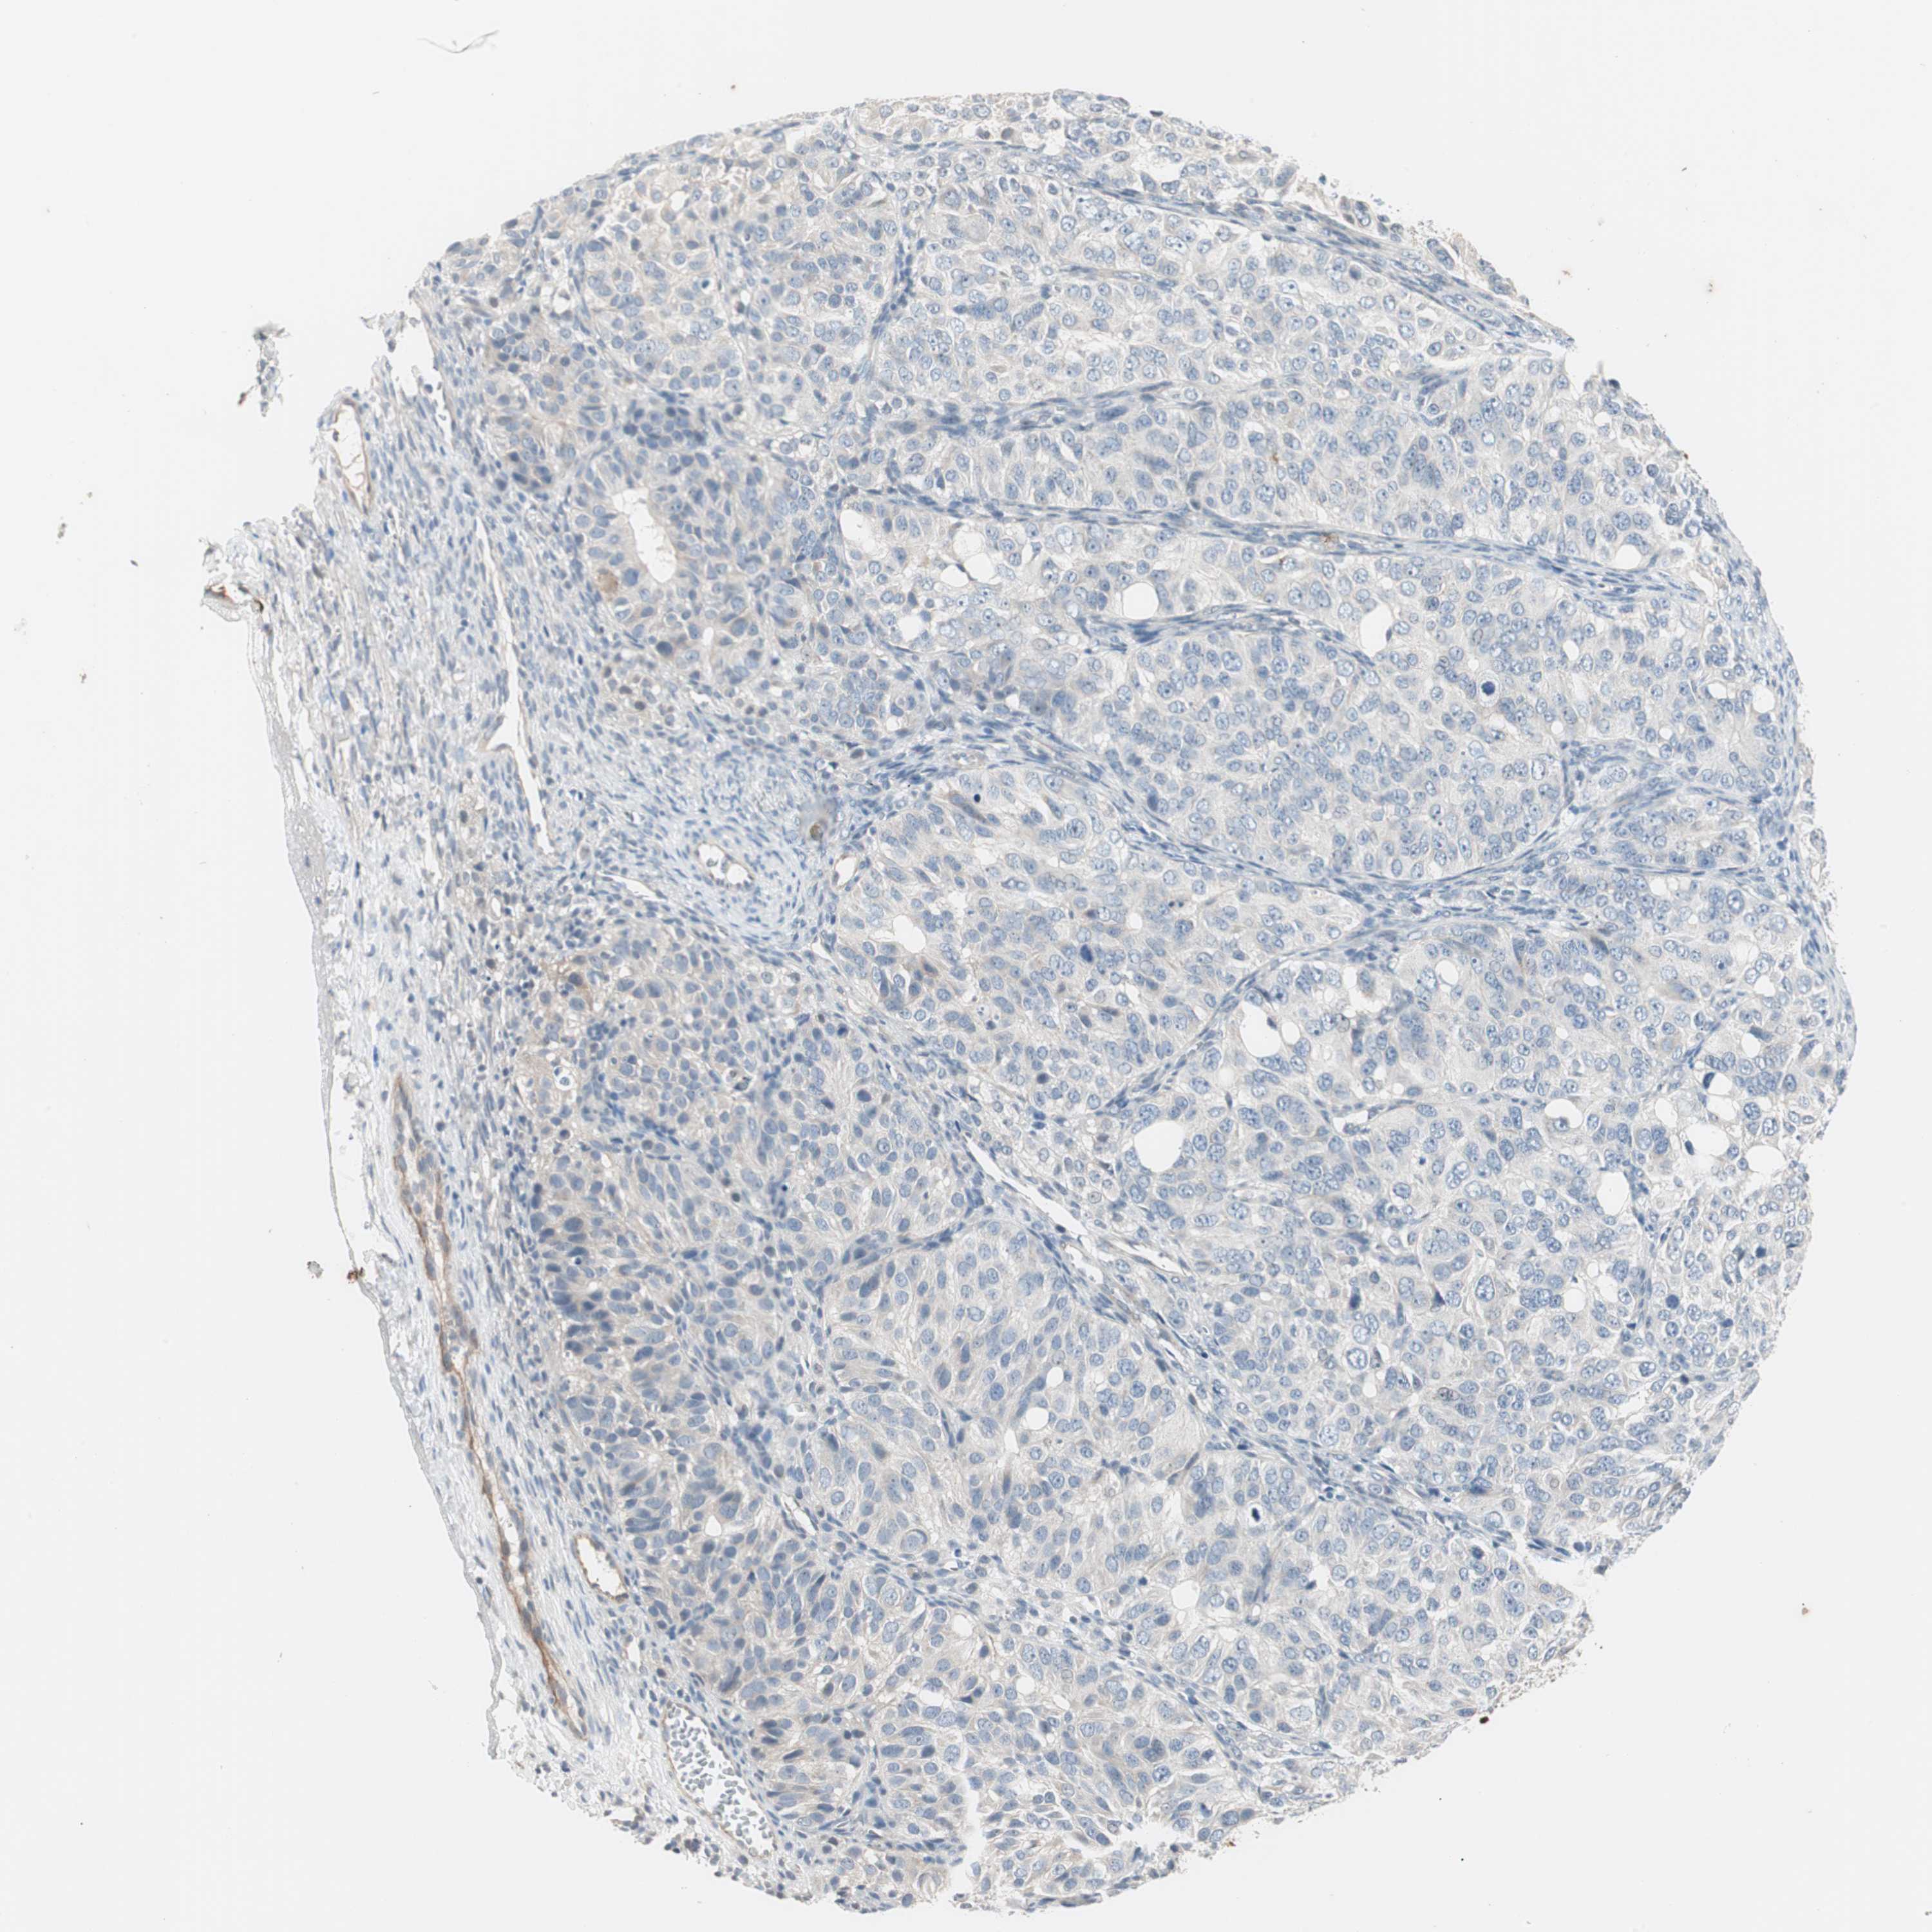

OVARIAN CANCER - Protein expressioni

A mouse-over function shows sample information and annotation data. Click on an image to view it in a full screen mode. Samples can be filtered based on level of antibody staining by selecting one or several of the following categories: high, medium, low and not detected. The assay and annotation is described here.

Note that samples used for immunohistochemistry by the Human Protein Atlas do not correspond to samples in the TCGA dataset.

Antibody stainingi

Antibody staining in the annotated cell types in the current human tissue is reported as not detected, low, medium, or high, based on conventional immunohistochemistry profiling in selected tissues. This score is based on the combination of the staining intensity and fraction of stained cells.

Each image is clickable and will lead to virtual microscopy that enables deeper exploration of all samples and also displays staining intensity scores, fraction scores and subcellular localization as well as patient and tissue information for each sample.

Antibody HPA036348

Antibody HPA036349

Antibody CAB002422

Antibody CAB005258

Cystadenocarcinoma, serous, NOS

Carcinoma, NOS

Cystadenocarcinoma, mucinous, NOS

Carcinoma, endometroid